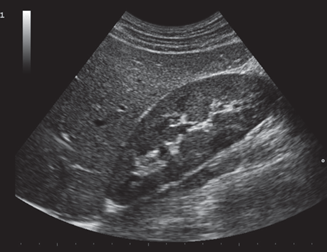

Sometimes referred to as sonography, ultrasound sends sound waves which then bounce off objects within the body and relay back to the sonographer the size of the object and whether it’s moving. For centuries, this technology has also been witnessed in nature where animals use sonar to send sound waves and interpret the returning echoes to detect distance and possible movements in objects. Since its application within medicine, the use of ultrasound has enabled medical experts the ability to capture a moment in time for patients, effectively visualizing anatomy and pathology otherwise unseen without a scalpel.

While ultrasound is commonly known for its use during pregnancy, it plays a vital role in countless other applications such as vascular, abdominal and cardiac imaging. Ultrasound guided procedures allow clinicians to properly identify blood vessels before inserting intravenous catheters, to correctly guide needles during a biopsy or to see heart structures in motion before doing more extensive cardiac procedures.